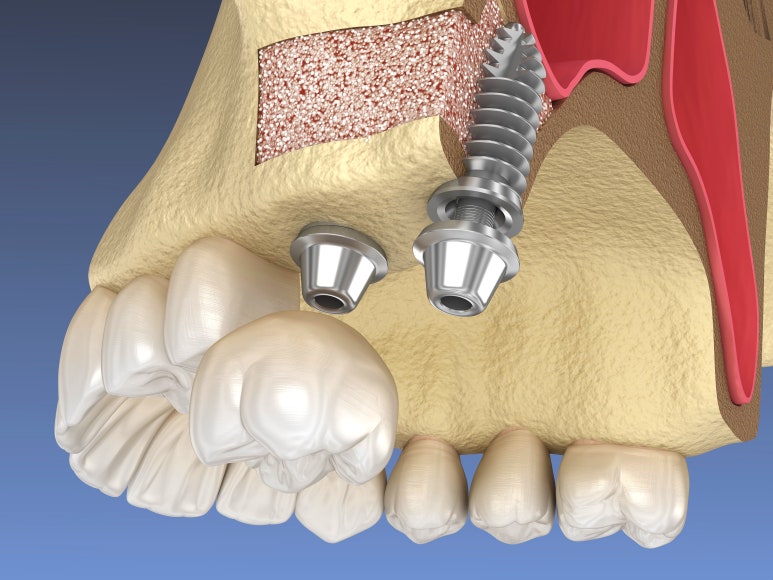

옆에서 접근하는 측방 접근법

라테랄 어프로치

앞서 말씀드린 크레스탈 어프로치와 달리 뼈이식 양이 많거나, 이상한 구조물이 있다면 '라테랄 어프로치'로 진행해야 합니다.

이는 옆에서 구멍을 뚫고 들어가 수평으로 뼈를 이식하는 방법입니다.

아무래도 절개 부위가 크레스탈보다는 절개 부위가 넓어서 통증과 부기, 멍이 들 가능성이 커지게 됩니다.

따라서 될 수 있으면 절개를 최소화하는 시술자의 노하우와 술기가 필요합니다.